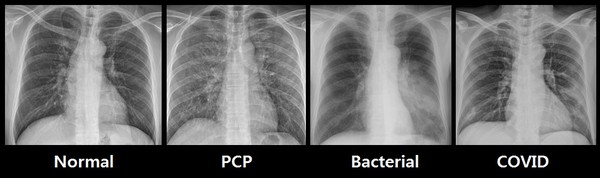

코로나19 관련 의료 데이터를 다량 보유하고 있는 대구가톨릭대학병원은 재이랩스의 메디라벨을 의료진들의 코로나19 감염 예측 및 흉부질환 판독을 돕는 영상 전처리 라벨링 프로그램으로 사용할 예정이다.

코로나19 폐렴의 병변은 다양한 형태를 띄고 있어 딥러닝 기술의 데이터라벨링으로 정확한 결과를 도출하는 것이 중요하다. 기존 의료 라벨링 소프트웨어 대비 속도와 정확도면에서 뛰어난 성능을 자랑하는 메디라벨은 CT, X-ray 등의 의료 영상에서 신뢰도 높은 데이터를 추출하는데 용이하며 데이터라벨링 과정에서의 인력 수급 문제도 효율적으로 개선할 수 있다.

또 메디라벨은 코로나19로 발생하는 폐, 흉부 질환 이외의 다양한 분과에도 확대 적용 가능해 새로운 감염병의 조기 대응 시스템 구축에도 많은 도움을 줄 것으로 기대되고 있다. 대구가톨릭대학병원은 다각적으로 축적된 감염병 의료데이터를 기반으로 환자들에게 국내 환경에 적합한 최적화된 의료 서비스를 제공한다는 방침이다.